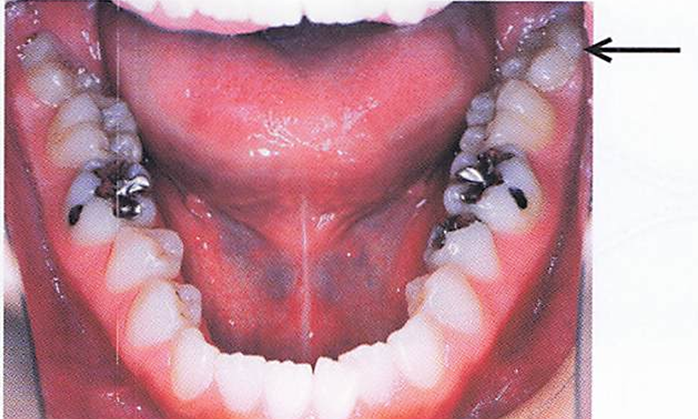

口腔内写真(別冊午後N。.2)を別に示す。矢印で示すのはどれか。1つ選べ。